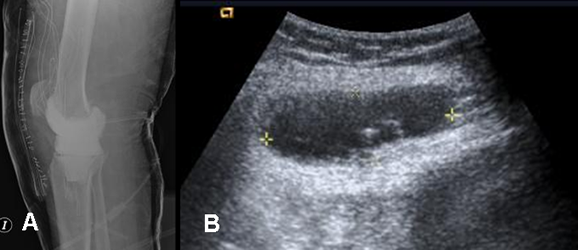

Fig 18. Absceso.

A: Rx lateral y B: Ecografía. PostQx reemplazo de rodilla. El paciente presenta mala evolución con dolor y limitación funcional, encontrando colección hipoecoica con ecos internos en los tejidos blandos.